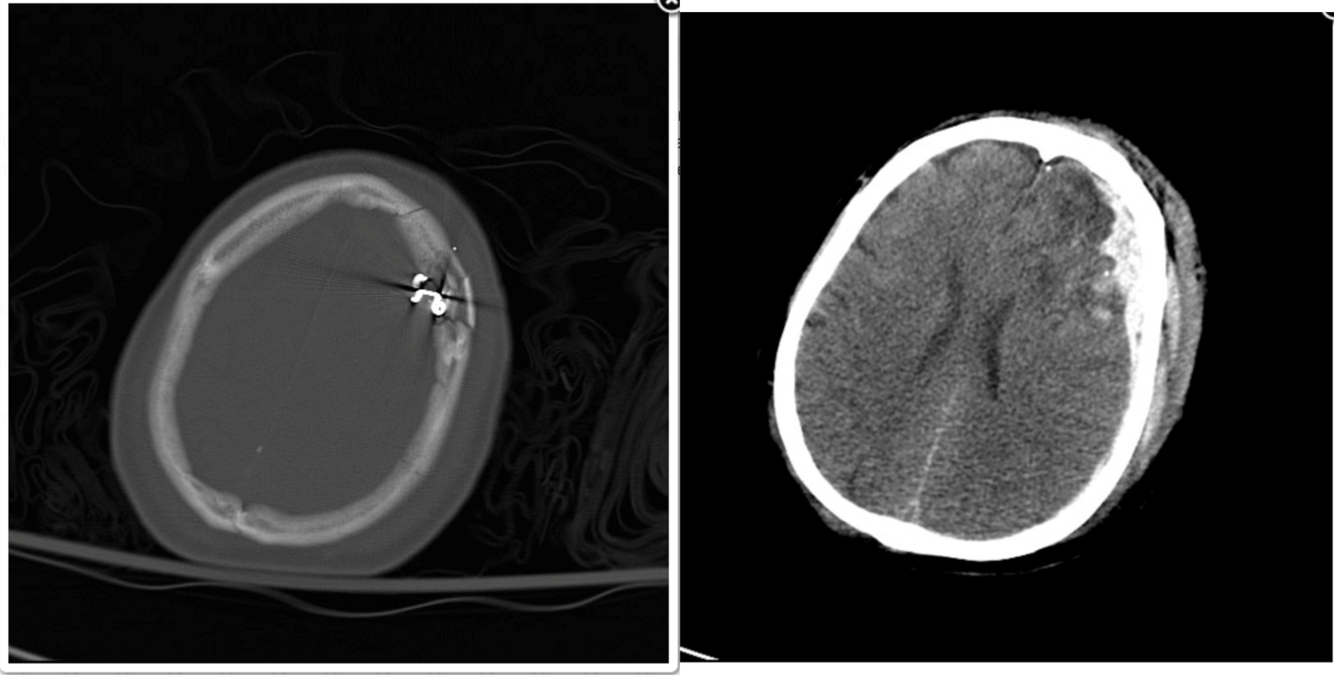

A 17 year old sustains a gunshot wound to the head. On examination, he has decorticate posturing on the right and he localizes on the left. His left pupil is 2 mm larger than the right but is still reactive. His non-contrast head CT (see figures) demonstrates metal and bone fragments within the left frontal region with an associated subdural hematoma with midline shift. What is the most appropriate management of this patient?

a. Superficial debridement of wound

b. Right frontal ventriculostomy placement

c. Craniotomy, hematoma evacuation, removal of all bone and metal fragments

d. Craniotomy, hematoma evacuation, superficial debridement

e. Expectant care

A